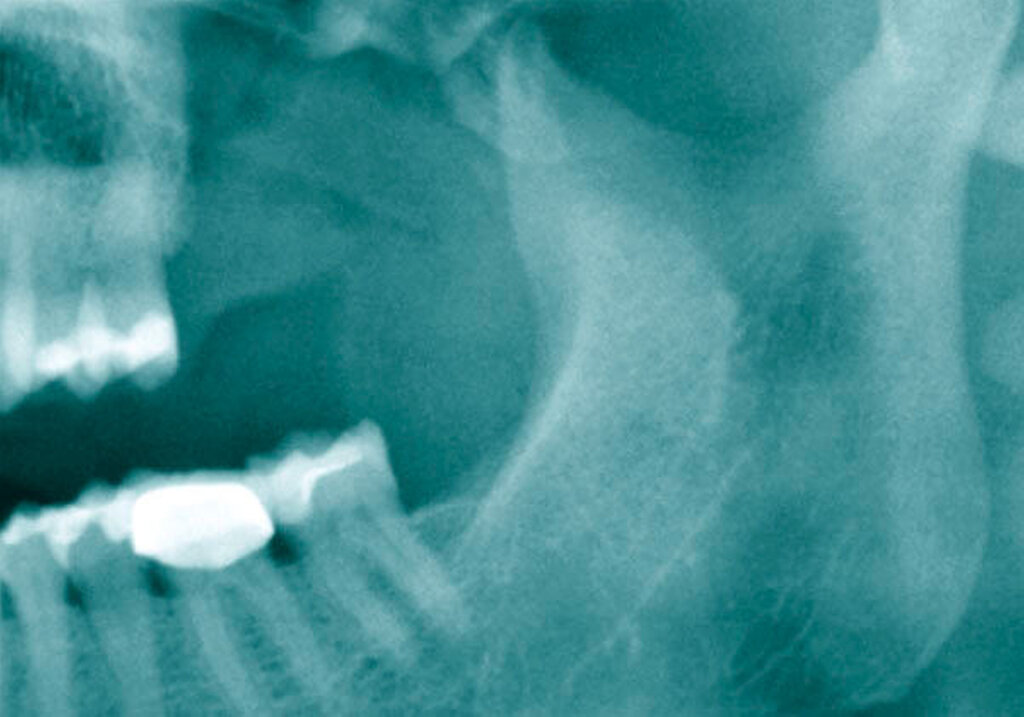

Als sich die Patientin an der Universitätsmedizin vorstellte, erfolgte primär die Anfertigung einer Computertomografie (CT) des Kopfes mit Kontrastmittel, in der sich eine vollständige Verschattung der linken Kieferhöhle sowie eine apikale Transluszenz an Zahn 26 darstellte (Abbildung 1).

Die Allgemein- und Familienanamnese der Patientin war bis auf eine medikamentös eingestellte Hypothyreose unauffällig. Extraoral bestand kein auffälliger Befund, insbesondere keine Druckdolenz oder Nervdefizit über der Kieferhöhle links. In Regio 27 zeigte sich eine Mund-Antrum-Verbindung nach frustranem Deckungsversuch, aus der sich seröse Flüssigkeit entleerte (Abbildung 2). Der Zahn 26 reagierte negativ auf Perkussion und war avital. Nach sorgfältiger Aufklärung erfolgte die Resektion des Befunds in Intubationsnarkose. Folgend auf die Extraktion des Zahnes 26 (Abbildung 3) wurde eine Kastenresektion der linken Maxilla von distal des Zahnes 25 bis in den Tuberbereich bei makroskopischem Einhalten eines Sicherheitsabstands von 0,5 cm durchgeführt. Das narbig anmutende Gewebe in der Kieferhöhle wurde ausgeschält und en bloc mit dem Oberkieferresektat entfernt (Abbildung 4). Der Knochen wurde hier belassen, da er klinisch und radiologisch nicht infiltriert war.

Der Defekt wurde mit einer lokalen Lappenplastik gedeckt (Abbildung 5), eine vorab angefertigte Verbandsplatte zum Wundschutz eingegliedert. Die abschließende histologische Auswertung (Abbildung 6) bestätigte, dass es sich bei dem kompletten Resektat um das bereits ex domo vor-diagnostizierte, teils plexiforme Ameloblastom handelte. Aufgrund der Größe des Tumors erfolgte ein Staging mittels CT-Thorax und Abdomen, das jedoch keinen Nachweis einer Metastasierung erbrachte. Bei mikroskopisch knappen Sicherheitsabständen nach palatinal sowie an der Nasenscheidewand und zur Orbita hin wurde die Patientin über ein differenzial-therapeutisches Vorgehen mit radikal-chirurgischem Vorgehen versus engmaschige klinische und radiologische Nachkontrollen aufgeklärt. Die Patientin entschied sich nach eingehender Aufklärung für die engmaschigen Nachkontrollen. Eine ossäre Rekonstruktion (Abbildung 7) wird derzeit von der Patientin nicht gewünscht.